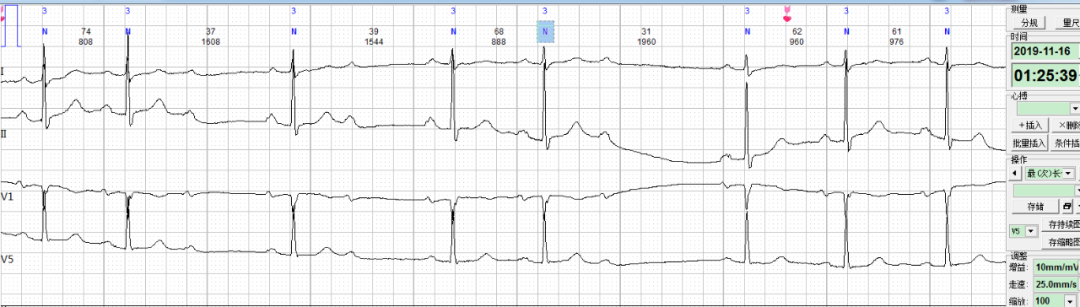

每日一图丨NO.675 请判断患者出现何种心电异常改变?乐普医疗AI关注2021-02-05 20:49 心电图解析(NO.674)今日读图(NO.675)患者朱某,女,78岁,住院患者。心电监护到如下片段,如何分析诊断?诊断完毕后要记得将答案写在留言区哦 浏览 45点赞 评论 收藏 分享 手机扫一扫分享分享 举报 评论图片表情视频评价全部评论推荐 一图流:Python所有内置异常Crossin的编程教室0一图流:Python所有内置异常Crossin的编程教室0每日一皮:代码出现Bug的三种表情!公众号程序猿DD0每日一皮:重构时总会出现的惊喜.......公众号程序猿DD0每日一皮:当我在重构时,总是有惊喜出现.......公众号程序猿DD0OddBall-图异常点检测AI入门学习0每日趣图:一夜速成学编程的秘籍,请收好程序员私房菜0每日一皮:新年好...公众号程序猿DD0每日趣图:硬核小学生写代码太枯燥武哥愿意与你一起共享点点滴滴的快乐这里是「 每日趣图 」专栏希望在枯燥中带给大家带来一份乐趣硬核小学生 ☟ ☟ ☟图片源自网络,仅作分享,如有侵权,请联系删除哦!关注我的视频号不要错过趣味视频友情...每日一荐 2021-03 月刊脑洞前端0点赞 评论 收藏 分享 手机扫一扫分享分享 举报